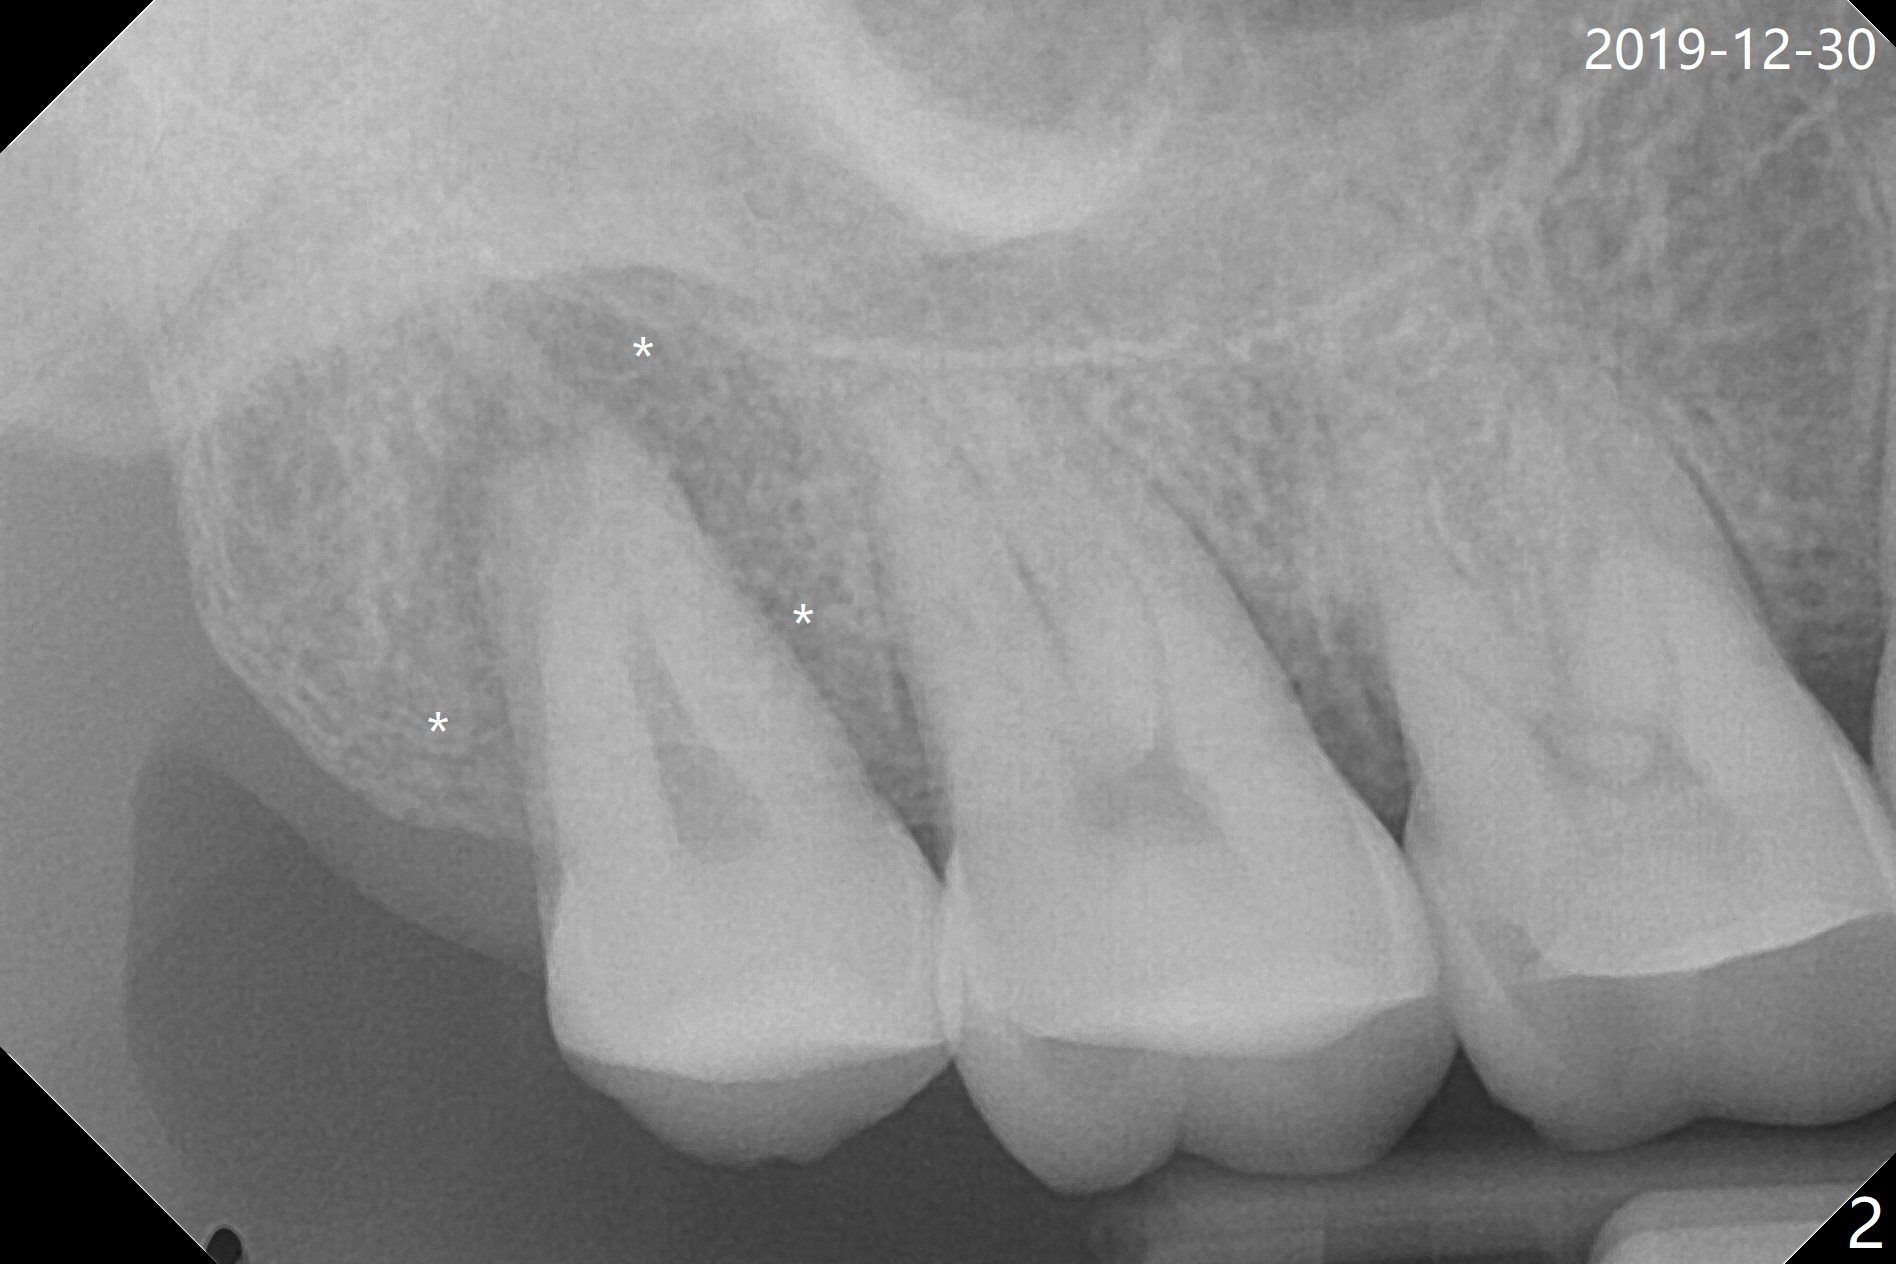

A 56-year-old woman returns to clinic with chief complaint of upper right discomfort (Fig.1) 9 months post #15 implant placement. Clinical exam does not reveal significant finding (periradicular radiolucency (PRRL) at #1 (*) is neglected). Six months later, PRRL at #1 is enlarged (Fig.2 *) with palatal gingival recession, pockets and BOP. The tooth is extracted; its palatal plate is lost, which is consistent with CT taken ~ 1 year earlier (Fig.3). Moreover, the palatal root is incidentally found to be have fractured at #2 (Fig.3,5 *), in the same manner as the tooth #15. Bone loss and root fracture are related to bruxism. Since the tooth #32 is present, an immediate implant could have been placed at #1 (Fig.4).